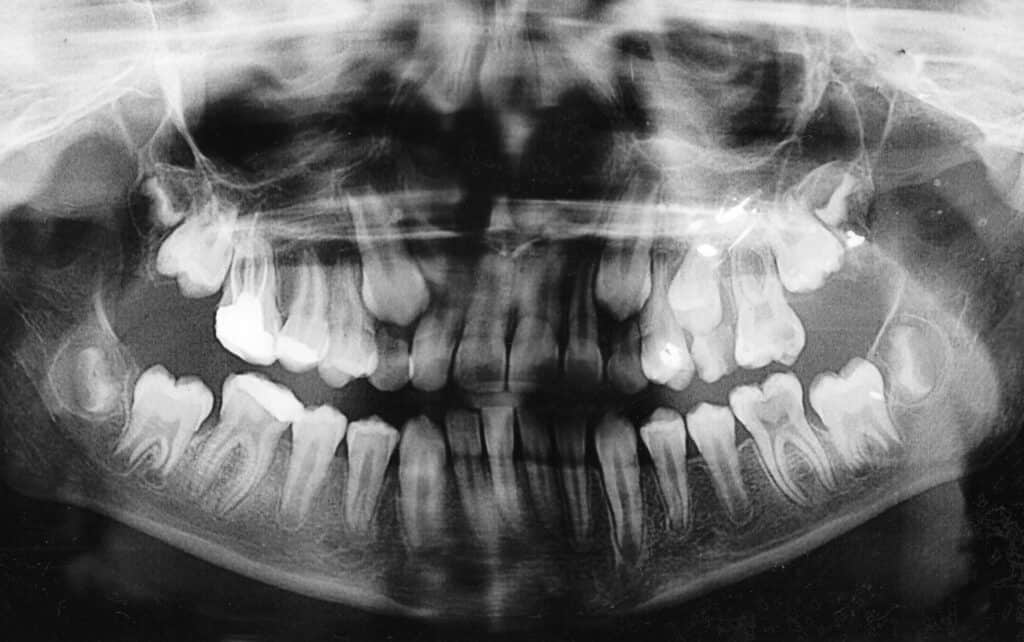

Orthopantomogram of a 12-year-old child. The upper canines and second molars have erupted while the first teeth are still in place. Why Treatment is Essential

Impacted canines are upper teeth (typically the cuspids) that fail to erupt fully into the mouth due to crowding, abnormal positioning, or other factors. Canines are crucial for maintaining alignment, supporting the structure of the mouth, and aiding in chewing. Left untreated, impacted canines can disrupt surrounding teeth, affect bite balance, and lead to further complications.

An impacted canine can press on neighboring teeth, altering alignment and potentially leading to pain, cyst formation, or bone loss. Early diagnosis and treatment are crucial to ensuring that impacted canines erupt properly, minimizing future dental complications, and supporting optimal oral health. At Precision Oral Surgery & Implant Center, our team evaluates each case with careful imaging and treatment planning to create the most effective approach for each patient.